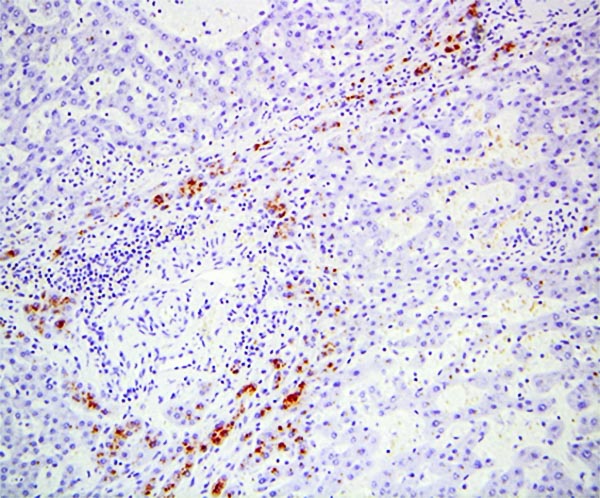

The explant showed a nodular liver with areas of sinusoidal dilatation, and occasional incomplete septae, but no evidence of cirrhosis. Rare florid ducts of PBC are present but there is mild ductopenia that came down to approximately just 20% of the terminal bile ducts; the larger bile ducts appear normal as are most of the small/terminal bile ducts. Several small portal tracts however have increased portal and occasionally periportal fibrosis and no visible portal veins. The larger portal tracts often have small portal veins when compared with the corresponding hepatic artery or bile duct, with thickening of the veins walls (obliterative portal venopathy). Reticulin stain demonstrates nodularity not bordered by fibrous septae, the edge of the nodules having compressed reticulin fibers (NRH). Sections from the hilum demonstrate major but non-occlusive portal vein thrombus.

Non-cirrhotic portal hypertension from a combination of nodular regenerative hyperplasia (NRH), portal vein thrombosis, and obliterative portal venopathy (OPV) in a patient transplanted for Primary Biliary Cirrhosis